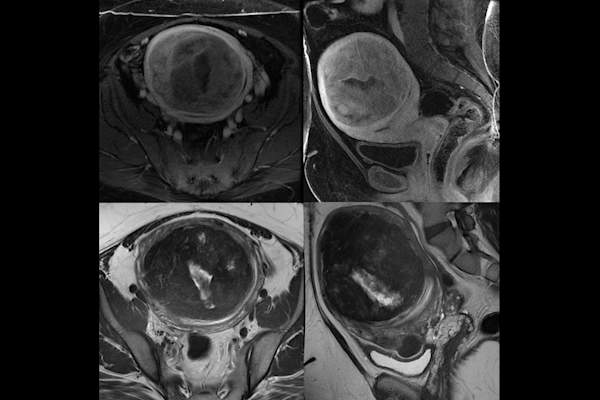

如何检测肌瘤?

如果你没有症状,你可以在每年的探视或怀孕期间的常规超声波检查中被诊断出来美国妇产科医师学会。在一次普通的盆腔检查中,医生可能会用手指感觉子宫肌瘤是子宫上的一个(通常是无痛的)肿块或肿块。你的医疗服务提供者也可以做成像测试,如超声波或核磁共振,以确认你有纤维瘤。